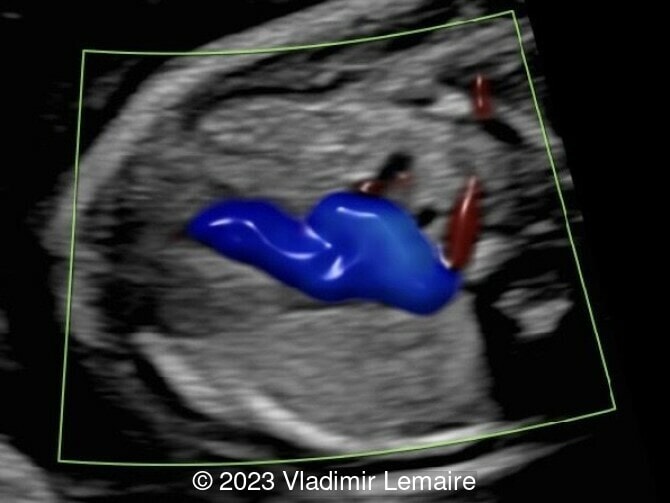

Aberrant right subclavian artery, seen in red, in a fetus at 20 weeks of gestation.

Image 3 Aberrant right subclavian artery, seen in red, in a fetus at 20 weeks of gestation.

Aberrant right subclavian artery, seen in green, in the same fetus.

Image 4 Aberrant right subclavian artery, seen in green, in the same fetus.